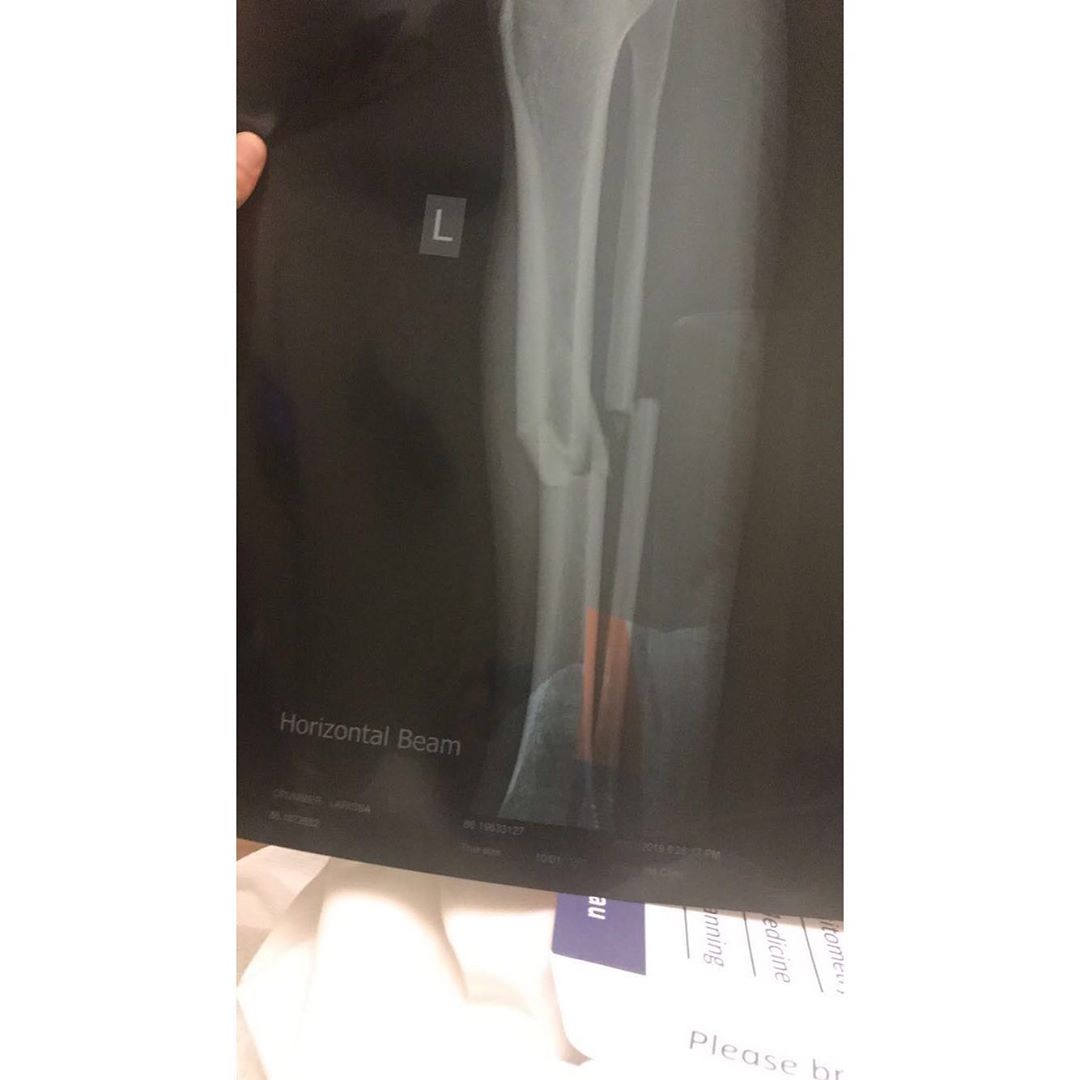

Crummer was later whisked away by ambulance and fears were confirmed when she later revealed she had suffered a broken tibia (shin bone) and fibula (calf bone) in her left leg and required the insertion of a steel rod via surgery.

The surgeon told her that her injury presented like one that had been sustained in a motor vehicle accident and Crummer would be in for a difficult healing process.

Firstly, she suffered with Compartment Syndrome due to the pressure in her leg from blood and fluid. She needed this drained and spent several weeks in hospital with an open leg, waiting for the swelling to go down. It was here that she was told if they had waited any longer to treat her, Crummer could've lost her leg.

Three months later, she suffered a bone infection so it was surgery number three to have her steel rod removed and replaced, and then later, she had to have all the screws in her leg taken out as they were causing discomfort.